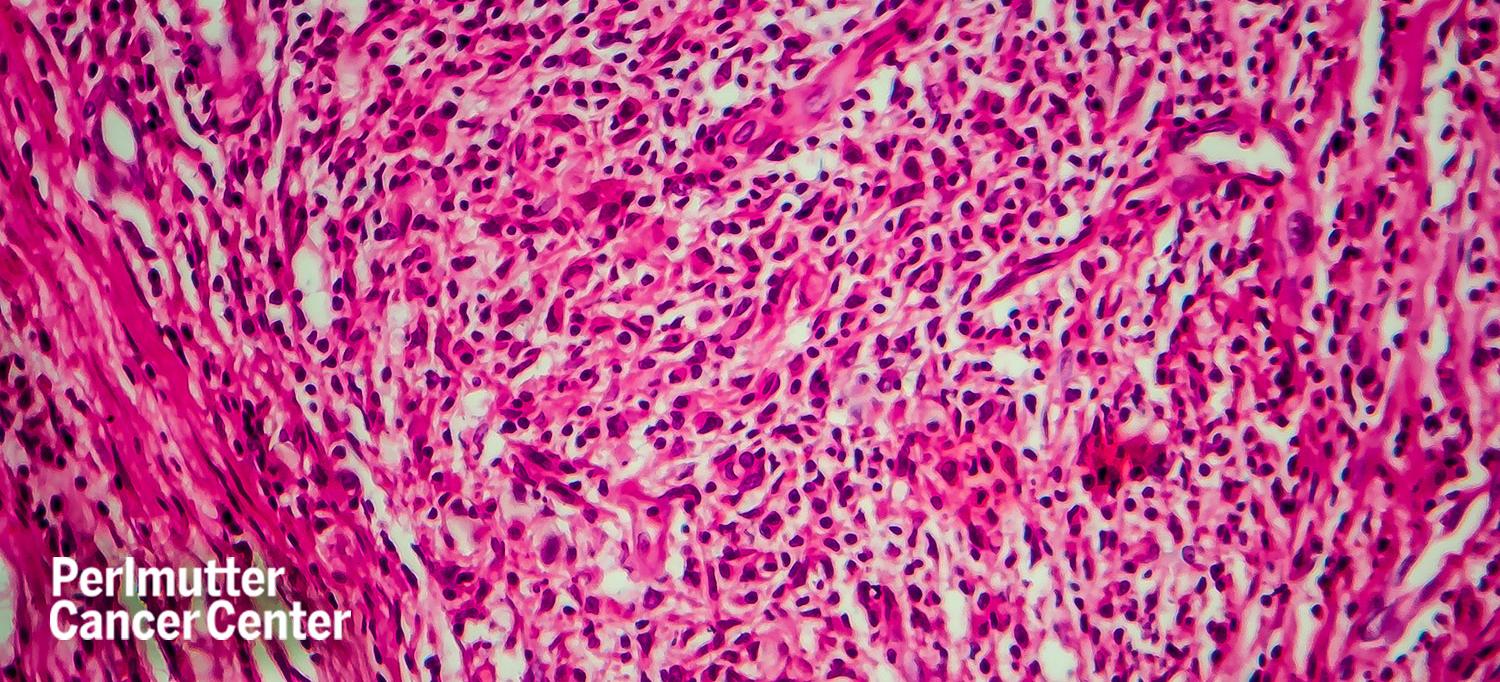

A common first sign of Waldenstrom macroglobulinemia is swollen lymph nodes, but up to 25 percent of patients do not experience any symptoms at the time of their diagnosis, Catherine S. Diefenbach, MD, associate professor in the Department of Medicine and director of the Clinical Lymphoma Program at NYU Langone Health's Perlmutter Cancer Center, tells Health.